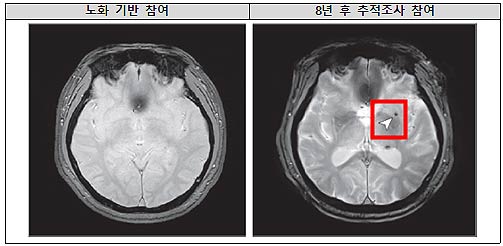

• 8년 후 뇌 미세출혈이 발생한 뇌영상 이미지

8년 후 뇌 미세출혈이 발생한 뇌영상 이미지

연구팀은 노화 심층조사사업 참여자 중 중장년층 1,441명을 8년 간 추적하여 수면무호흡의 중증도가 뇌 미세출혈 발생에 미치는 영향을 분석했다.